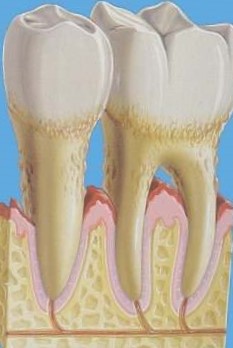

Анатомічна будова зуба включає видиму частину зуба (коронка) і поддесневую частина (шийка і корінь). Зовнішній шар зуба складається з емалі, яка вважається самою твердою тканиною організму. Зубна емаль покриває коронку і частково шийку для захисту пульпи від впливу високих і низьких температур. Оголення пришеечной області викликає у хворого напади болю від температурних і хімічних подразників.

- Оголення коренів зубів на половину висоти кореня має на увазі пломбування оголеною частини зуба або лікування кореневих каналів зуба. Незначна чутливість зубних тканин лікується за допомогою закриття оголеного ділянки реставраційним матеріалом. Інтенсивний больовий синдром вимагає депульпації, яка полягає в асептичному видаленні пульпи з подальшим заповненням кореневих каналів. Пломбування оголеного зуба має на увазі механічну обробку шийки зуба для утворення порожнини з рівними краями. Це необхідно для якісної фіксації реставраційного матеріалу.

Фото оголення на ½ довжини кореня різців нижньої щелепи